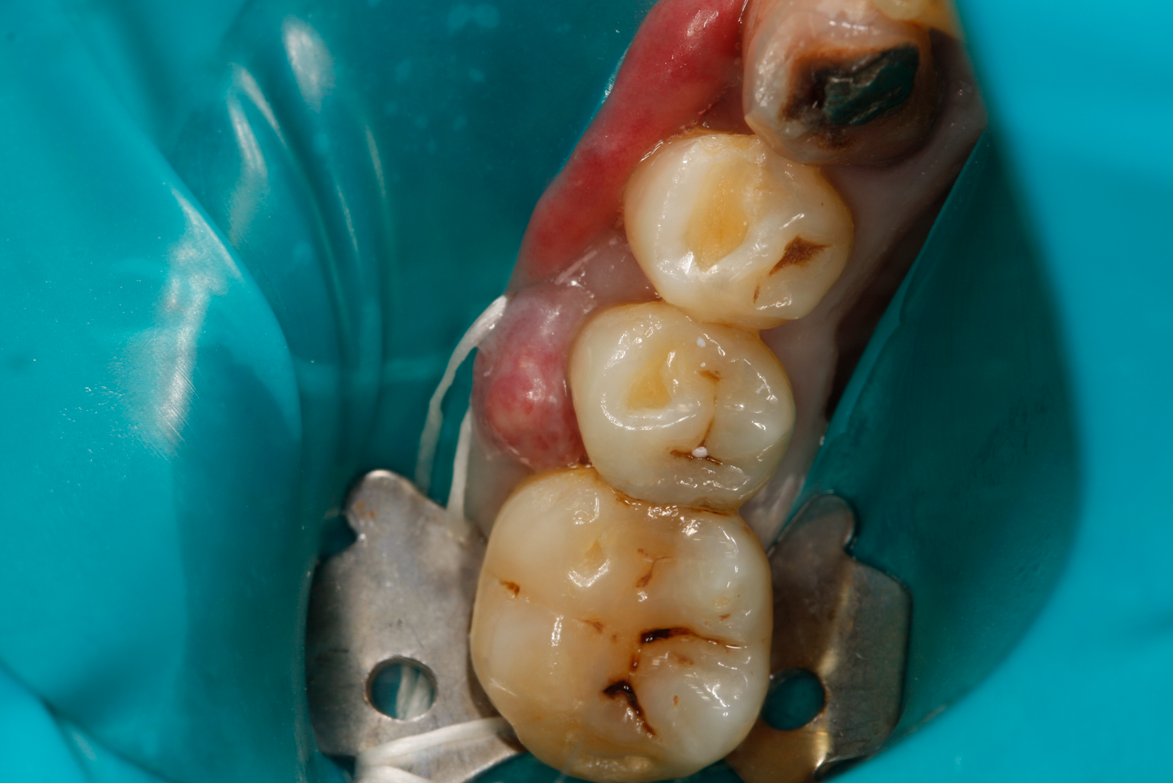

Case Study 2

A 42-year-old male patient with a unremarkable health history presented in the AEGD Residency Program clinic with a chief complaint of pain in the mandibular right posterior area. Fig- ure 30 shows an unremarkable occlusal view of tooth No. 29; however, the radiograph showed deep distal caries near the root canal (Figure 31). Several treatment options were discussed with the patient, including extraction, root canal therapy, post and crown, and a distal occlusal composite that would later serve as a "margin elevation" material following endodontic therapy and preparation for a distal occlusal ceramic inlay or onlay. The patient chose the latter option.

A deep distal occlusal preparation was performed and a matrix band (Paraband, Practicon) was placed again, such that no wedge needed to be placed (Figure 32). The Groman Etchmaster was utilized to remove biofilm as previously shown in Figure 12. A total etch technique with 37% phosphoric acid was employed (Figure 33), and after thorough rinse and damp dry, a universal adhesive (Scotchbond Universal, 3M) with MDP was applied and light-cured 40 seconds at 1,200 mw/cm2 due to the depth of the box form (Fig- ure 34). Figure 35 shows the dual-cure bulk-fill flowable composite (Bulk EZ Plus, Zest Dental Solutions) being injected into the deep box with a 20-gauge bendable needle. It is important to keep extrusion pressure on the plunger while withdrawing the needle to prevent bubbles or voids in the composite interface with the tooth structure. Overfilling by approximately 10% and smoothing the surface only with brushes promotes good marginal seal (Fig- ure 36). It is critical to not disturb the occlusal surface of any dual-cure bulk-fill flowable with an attempt to "soft sculpt," as that may create marginal voids.

Fig 30. Preoperative photograph of tooth No. 29.

Figure 30

Fig 31. Preoperative radiograph showing deep caries in canal. Restoration prior to endodontic therapy is required.

Figure 31

Fig 32. Preparation is completed, caries are removed, sand blasting with potassium carbonate is performed, and matrix band is placed.

Figure 32